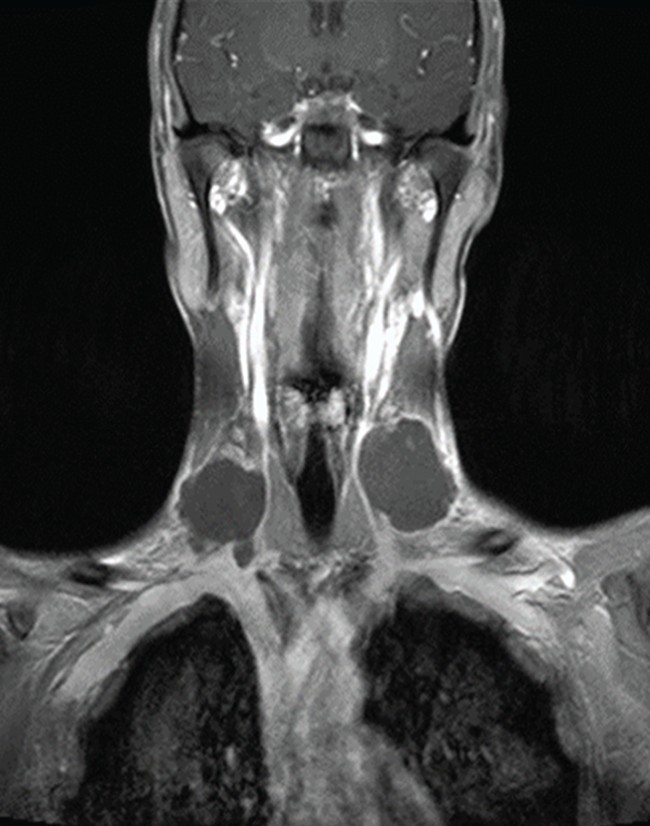

An MRI showed three large lumps around the ulcer, each measuring up to 5cm.

The patient also had two blood clots in his jugular vein.

Doctors examining him noted the lymph nodes – glands that help fight infections by trapping bacteria and bugs – in his neck were hard and swollen.

They also examined the large, crusted ulcer, which had spread across the base of his neck as well as into the deeper layers of his skin.